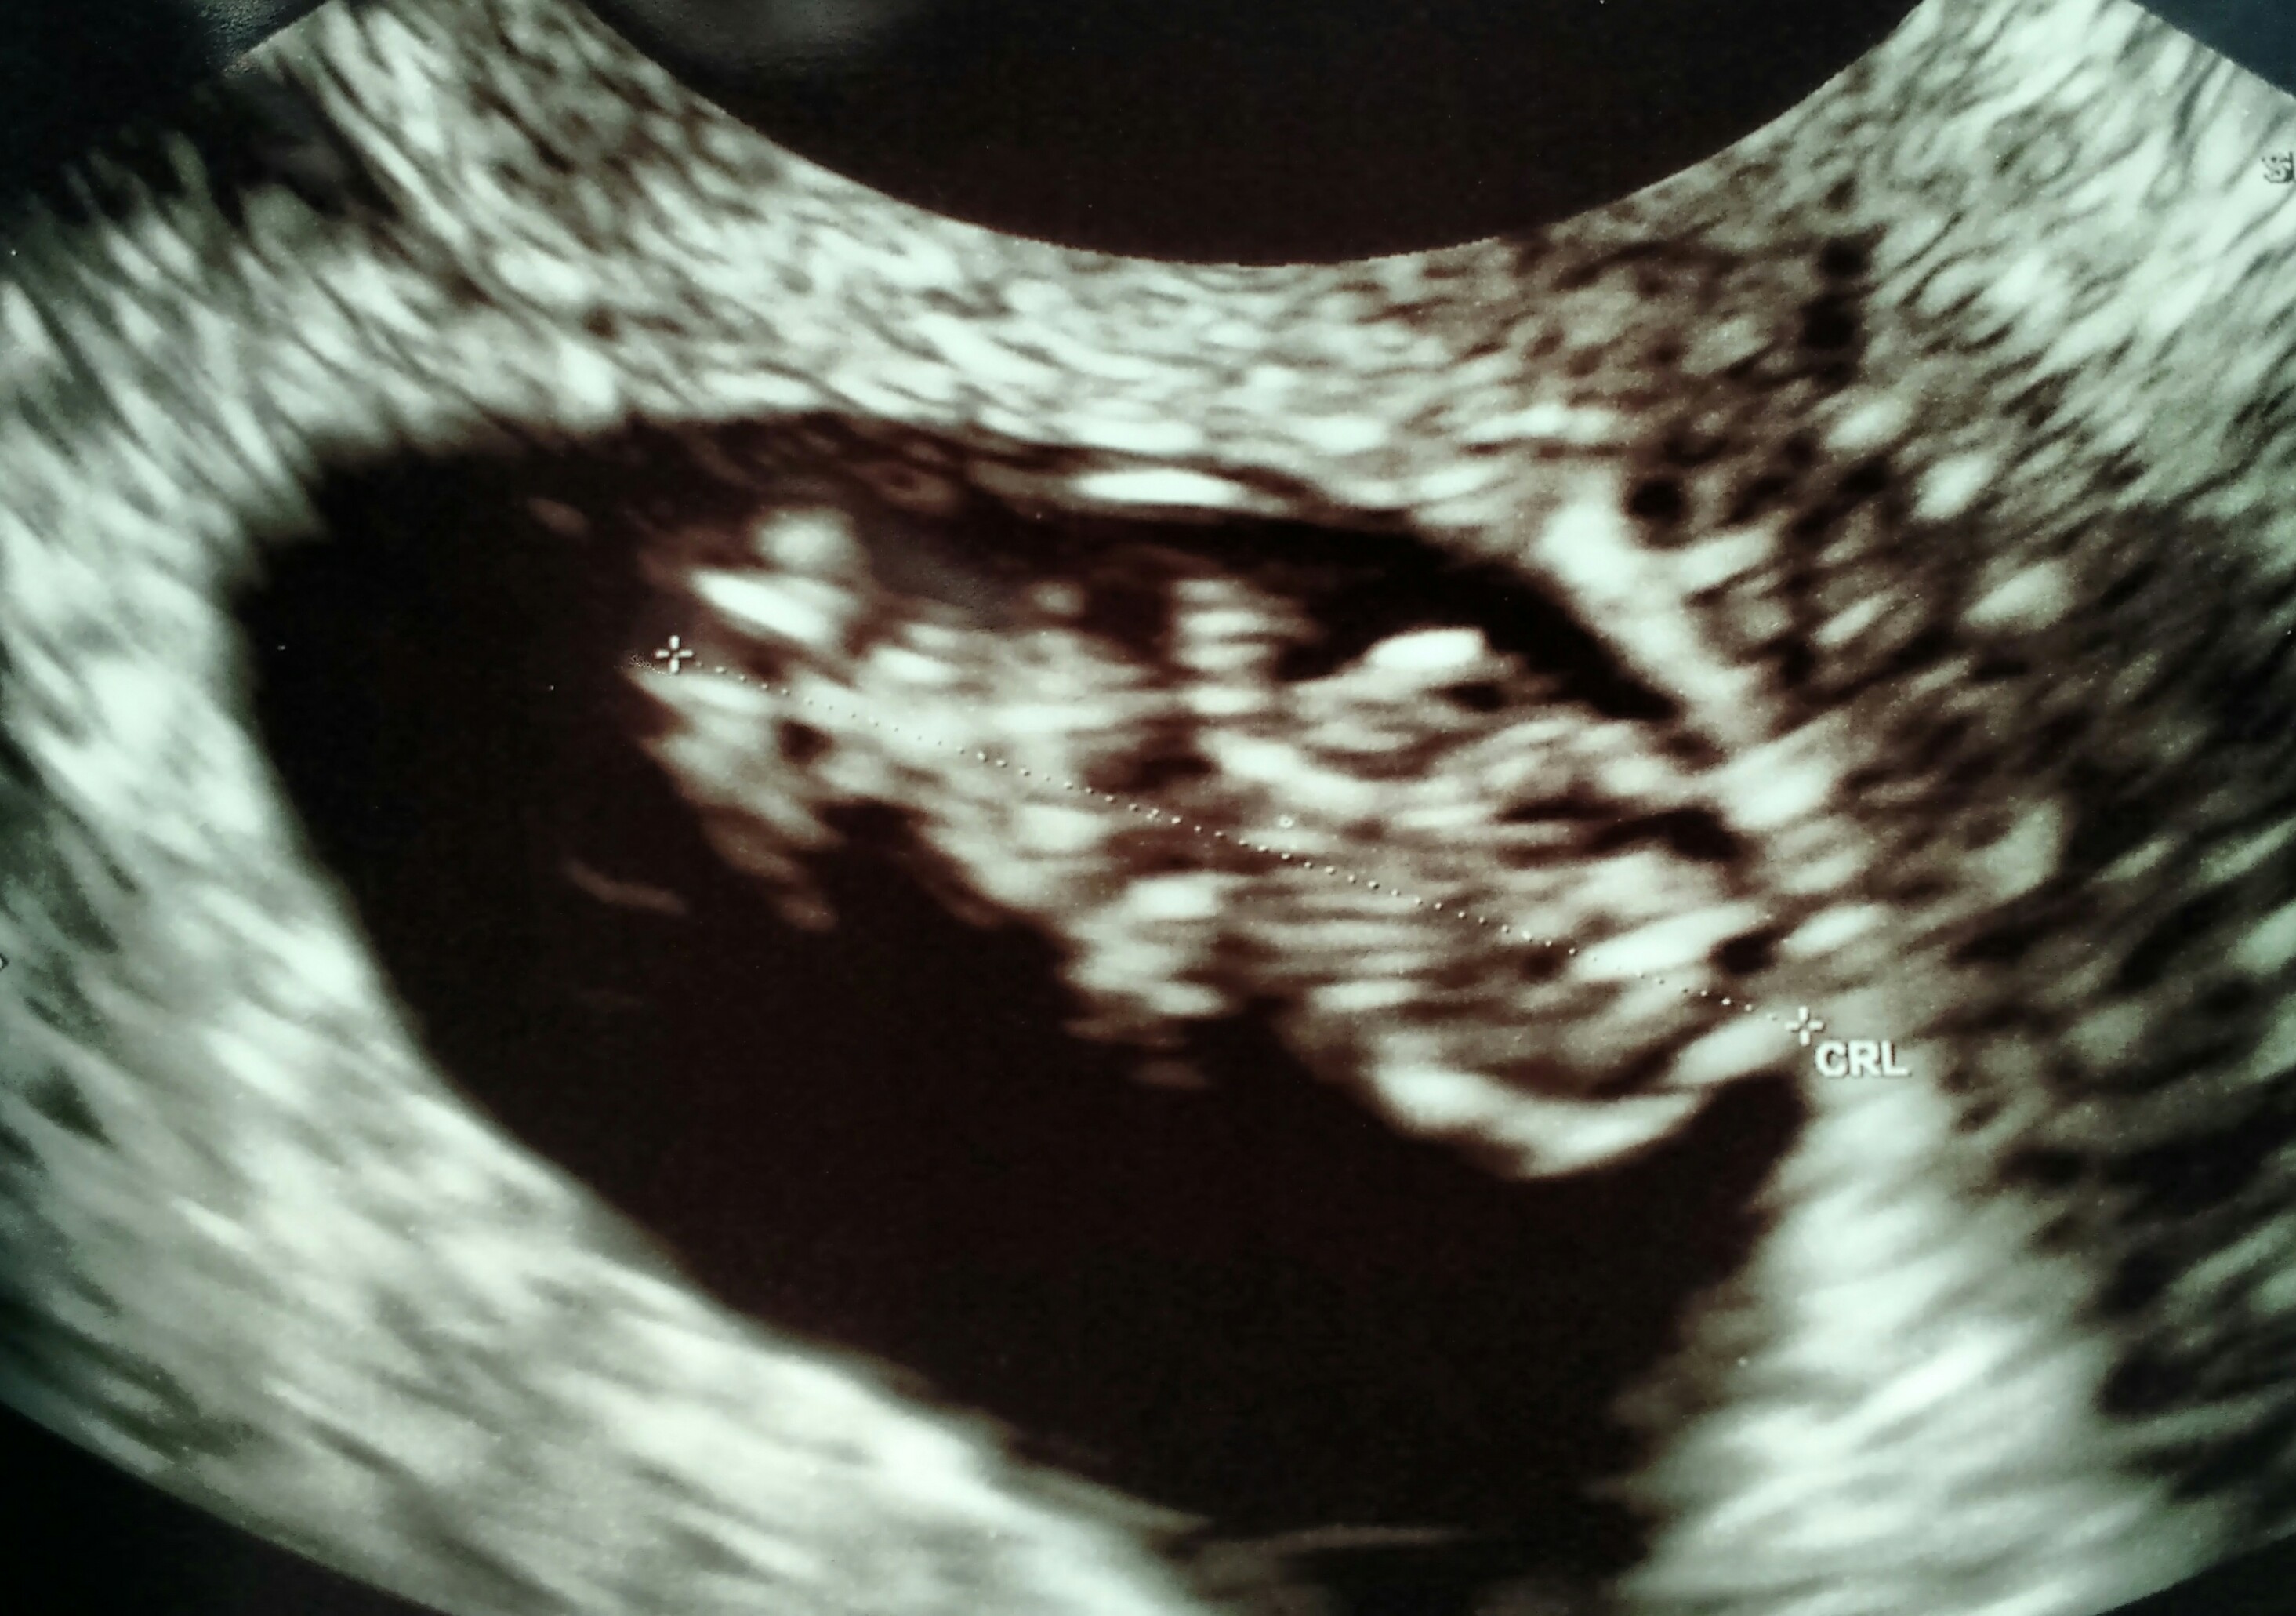

• I'm 10 weeks today. My due date is April 7th. This picture is actually from my second ultrasound that I got yesterday. I got my first one done at 7 weeks and 5 days due to some minor bleeding which they determined was from a small blood blister in my uterus. As of yesterday we got the good news that the blood blister has shrunk dramatically! So now my appointments will continue on as normal. The baby's heartbeat was 156 at my first appointment and yesterday it was 175. I'm not sure I can accurately describe how happy I was to see my little baby moving around on the screen yesterday! It's truly something magical.